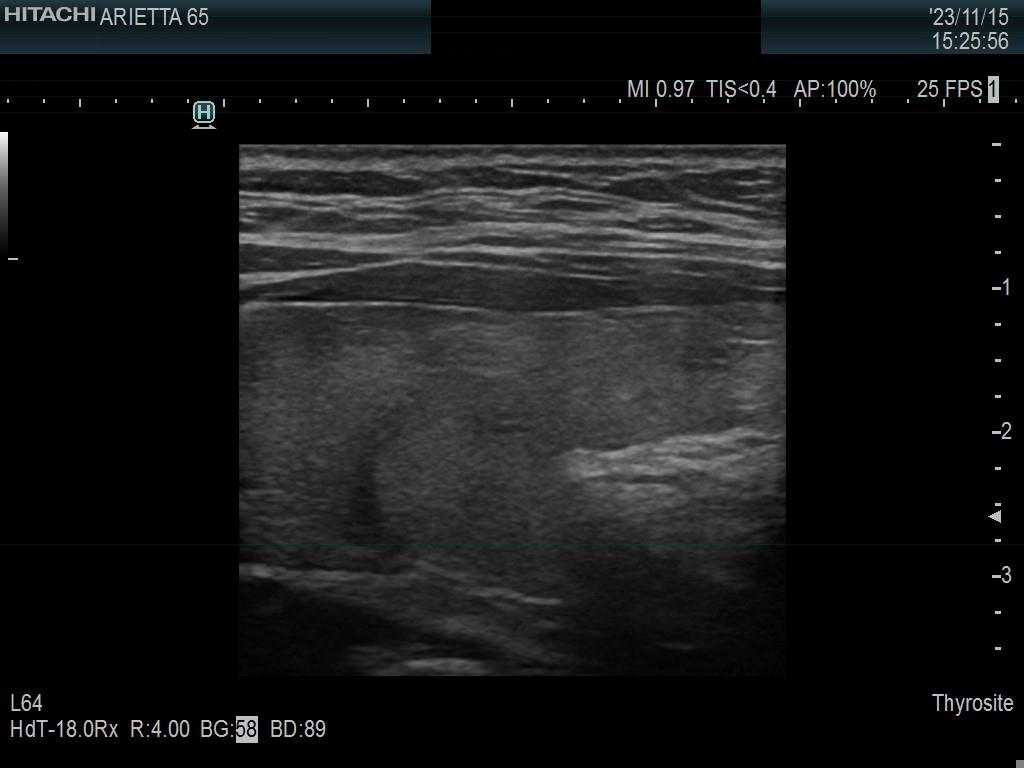

Ultrasonography. The thyroid was minimally hypoechoic. The echogenicity of the dorsal part of the left lobe where the nodule was previously described did not differ from other parts of the thyroid. There was a connective tissue running ventral to this part of the lobe and hypoechoic areas were found upper and dorsal to this. Neither halo nor perinodular blood flow was present.

The area in question did not correspond to a pathological nodule. It seemed to be circumscribed because of the presence of connective tissue and thyroid vessels.

A follicular tumor must have a capsule which ultrasound sign, either a complete halo and/or perinodular blood flow are present in more than 95% of cases. Both features were absent in this case.